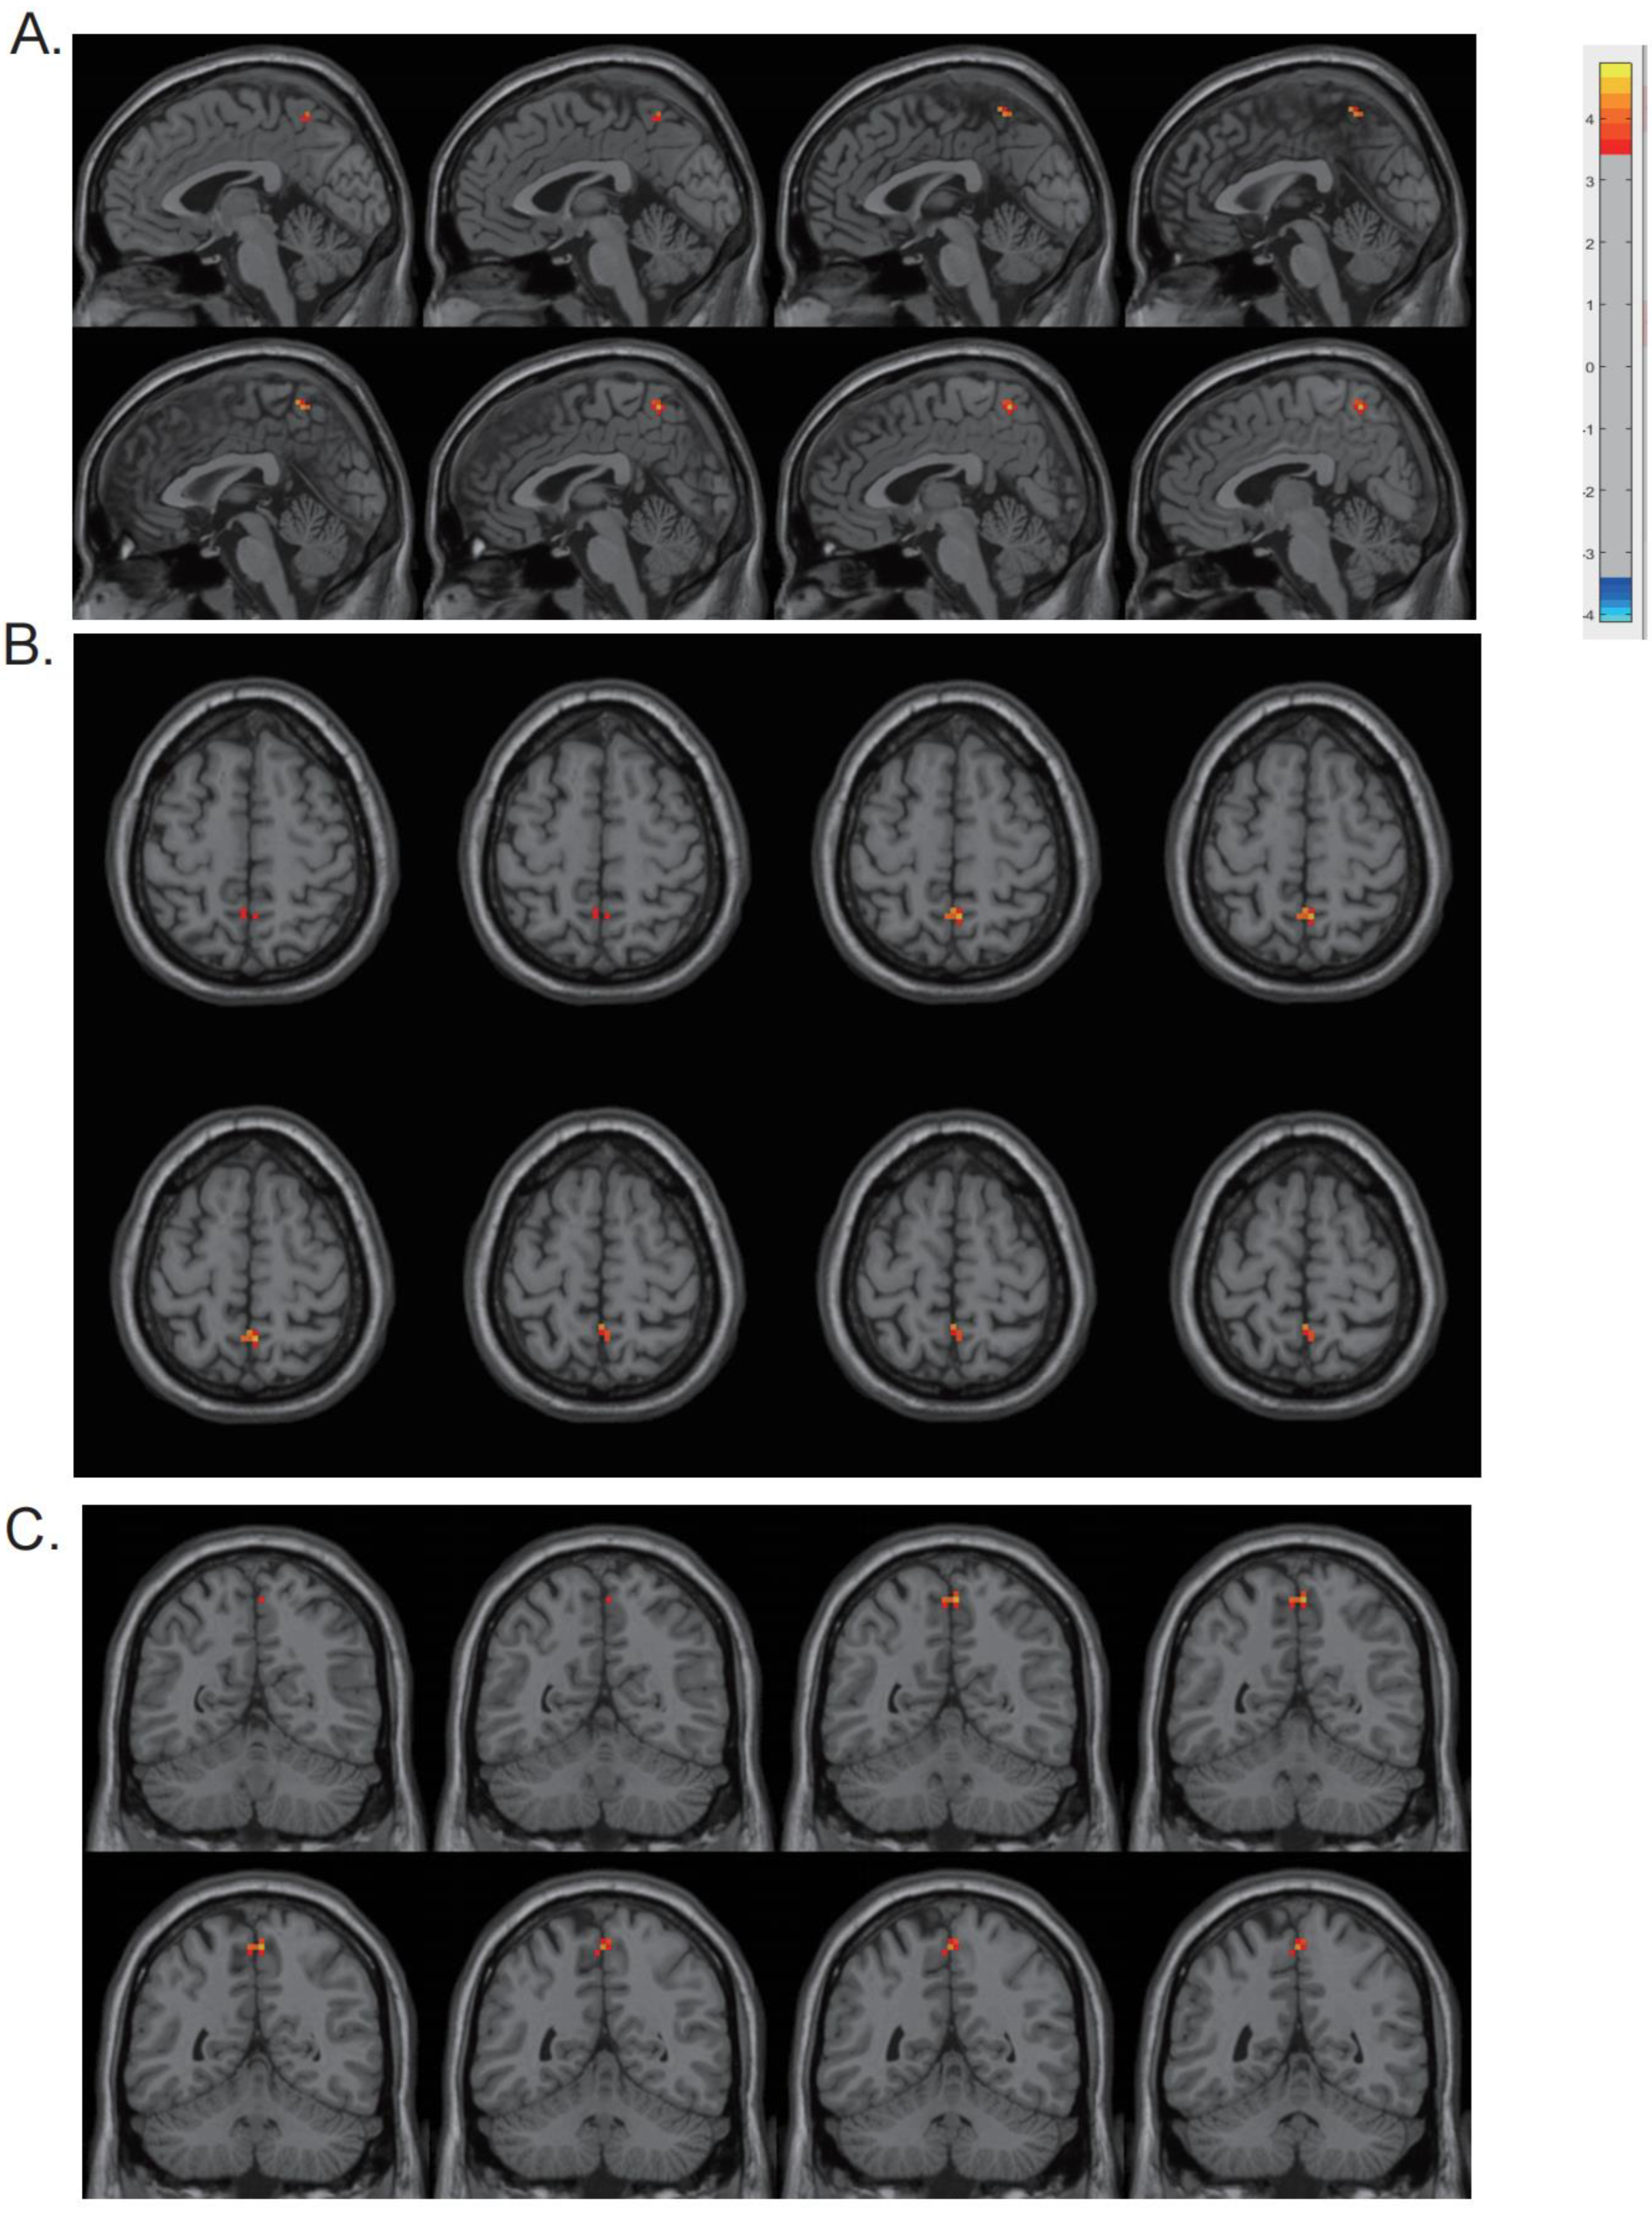

| Region | Cluster Size (Voxel) | MNI (x, y, z) | t-Value |

|---|---|---|---|

| Precuneus | 13 | (3, −54, 60) | 4.5626 |

3.3. DReHo Analysis and Correlation Analysis